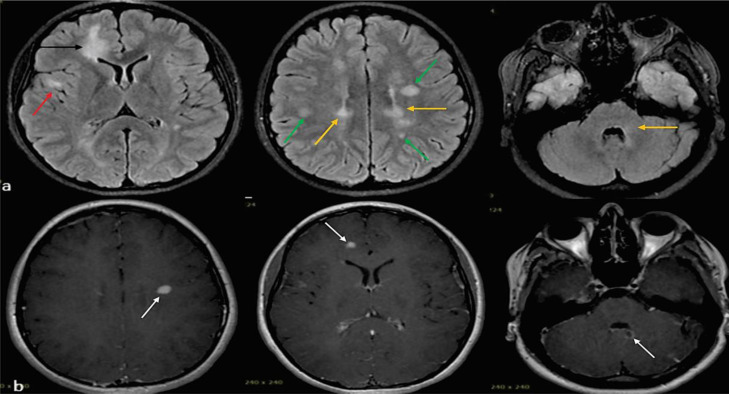

背景:多发性硬化症(MS)是导致年轻人非创伤性残疾的最常见原因。关于接种 2019 年冠状病毒病(COVID-19)疫苗后发生脱髓鞘事件的报道很有限。接种方法我们报告了所有在2021年9月至2022年6月期间新诊断为多发性硬化症且近期(≤6周)接触过国药集团(BBIBP-CorV)疫苗的患者(n = 8)。我们还查阅了截至 2023 年 9 月发表的相关文献。结果在研究期间,338 名新确诊的多发性硬化症患者到我们的多发性硬化症三级转诊中心就诊,其中 8 人(2.36%)在接种国药控股疫苗后首次脱髓鞘发作,中位间隔为 2 [2.0, 4.0] 周(性别比为 1:1,中位年龄:20.5 [18.0, 27.0] 岁)。除一名患者有潜在脱髓鞘病史和另一名患者有免疫性血小板减少性紫癜(ITP)家族史外,其他患者均无自身免疫/神经系统疾病的个人或家族病史。所有患者均有脱髓鞘性脑部磁共振成像病变,其中4人的颈脊髓受累。最常受影响的脑区是脑室周围和皮层下区域。所有患者的寡克隆带(OCB)均呈阳性,支持多发性硬化症的诊断。所有患者均被诊断为复发性多发性硬化症,并接受了单独或结合血浆置换的静脉甲基强的松龙(IVMP)治疗(3/8)。利妥昔单抗是最常用的疾病修饰治疗方法(3/8)。结论本研究提供了初步证据,证明国药控股疫苗与多发性硬化症初期表现之间存在潜在联系。然而,要证实这种关联并确定其潜在机制,还需要进行更大规模的对照组研究和长期随访。

Background: Multiple sclerosis (MS) is the most common cause of non-traumatic disability in young individuals. There are limited reports of developing demyelinating events following the coronavirus disease 2019 (COVID-19) vaccination. Methods: We reported all individuals (n = 8) with new MS diagnoses with recent exposure (≤ 6 weeks) to the Sinopharm (BBIBP-CorV) vaccine between September 2021 and June 2022. We also reviewed the related literature published as of September 2023. Results: Of 338 newly diagnosed patients with MS who attended our tertiary referral MS center during the study period, 8 (2.36%) had their first demyelinating attack with a median interval of 2 [2.0, 4.0] weeks following the Sinopharm vaccine (sex ratio 1:1, median age: 20.5 [18.0, 27.0] years). No personal or family history of autoimmune/neurological disorders was documented, except for one patient's history of a previous potential demyelinating event and another's family history of immune thrombocytopenic purpura (ITP). All patients had demyelinating brain MRI lesions, and 4 had cervical spinal cord involvement. The brain areas most commonly affected were the periventricular and subcortical regions. Positive oligoclonal bands (OCBs) in all patients supported the MS diagnosis. All patients were diagnosed with relapsing-remitting MS and received intravenous methylprednisolone (IVMP) alone or in combination with plasma exchange (3/8). Rituximab was the most frequently used disease-modifying treatment (3/8). Conclusion: This study provides preliminary evidence of a potential association between the Sinopharm vaccine and the initial manifestations of MS. However, further larger-scale studies with control groups and long-term follow-ups are needed to confirm this association and determine the underlying mechanisms.